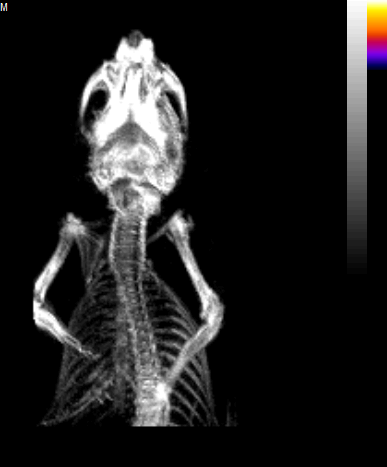

將小鼠左頸動脈血管暴露接觸氯化鐵,誘導(dǎo)血栓形成。隨后注射Targ-Cy7或Mut-Cy7熒光探針,45分鐘后在FLECT成像設(shè)備上掃描,可視化小鼠體內(nèi)的近紅外熒光三維分布。隨后立即進行X射線計算機斷層成像(CT),以確定小鼠的解剖結(jié)構(gòu),從而捕獲熒光信號的體內(nèi)精確定位。

結(jié)果表明,注射Targ-Cy7熒光探針后能夠清晰檢測到血栓(圖1B)。該信號定位于小鼠的左側(cè)頸動脈血管。